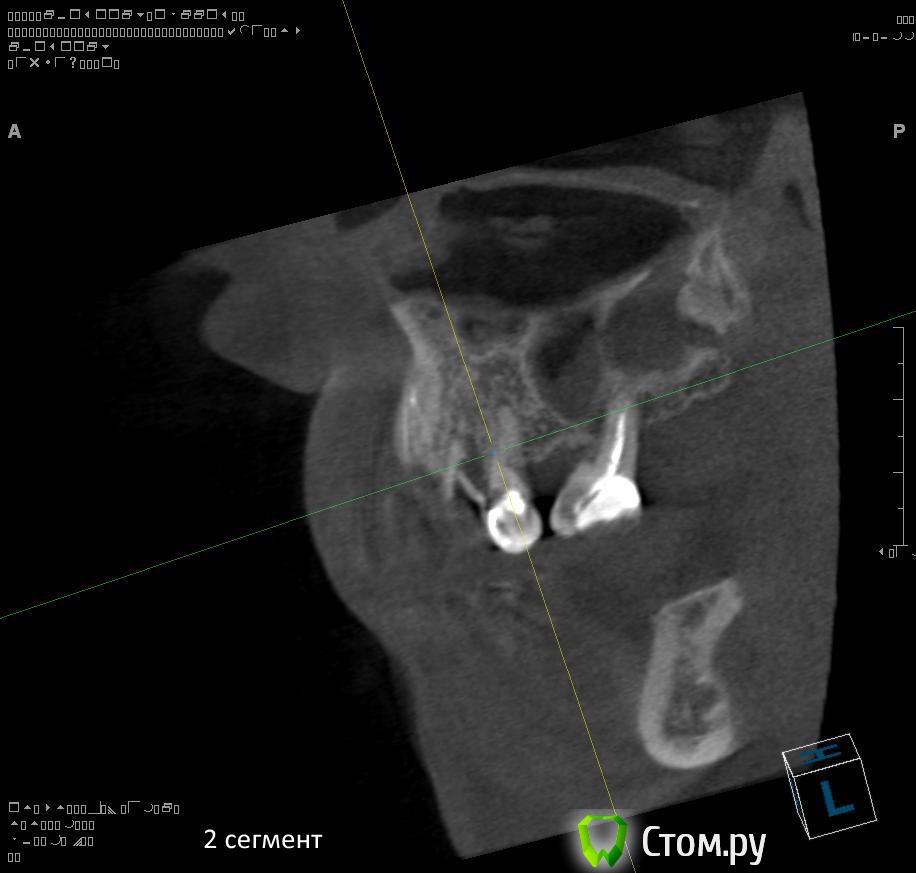

1. правильно ли я понимаю, что через 1,5 - 2 месяца после удаления 1.4 можно провести аугментацию (синус-лифтинг, латеральное окно, в первом сегменте, возможно с одномоментной установкой имплантатов)?

2. нужна ли в 1 сегменте дополнительная аугментация (по вертикали)?

3. в какие позиции должны быть поставлены имплантаты в 1 сегменте сбоку (1.7, 1.5)?

7. через 2-3 месяца после удаления 2.4, 2.5, 2.6 провести открытый синуслифтинг во втором сегменте возможно с одномоментной установкой имплантатов?

8. в какие позиции должны быть поставлены имплантаты во 2 сегменте (2.5, 2.6?)?